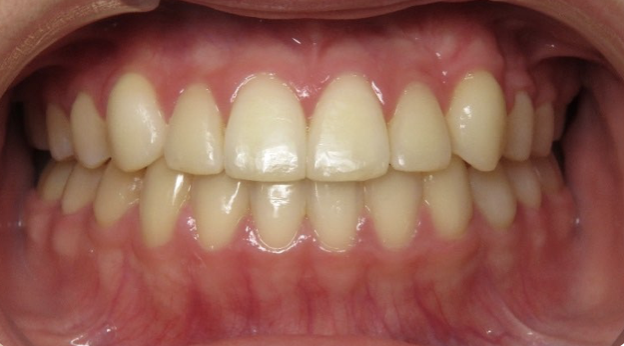

Underbite Before and After

Before